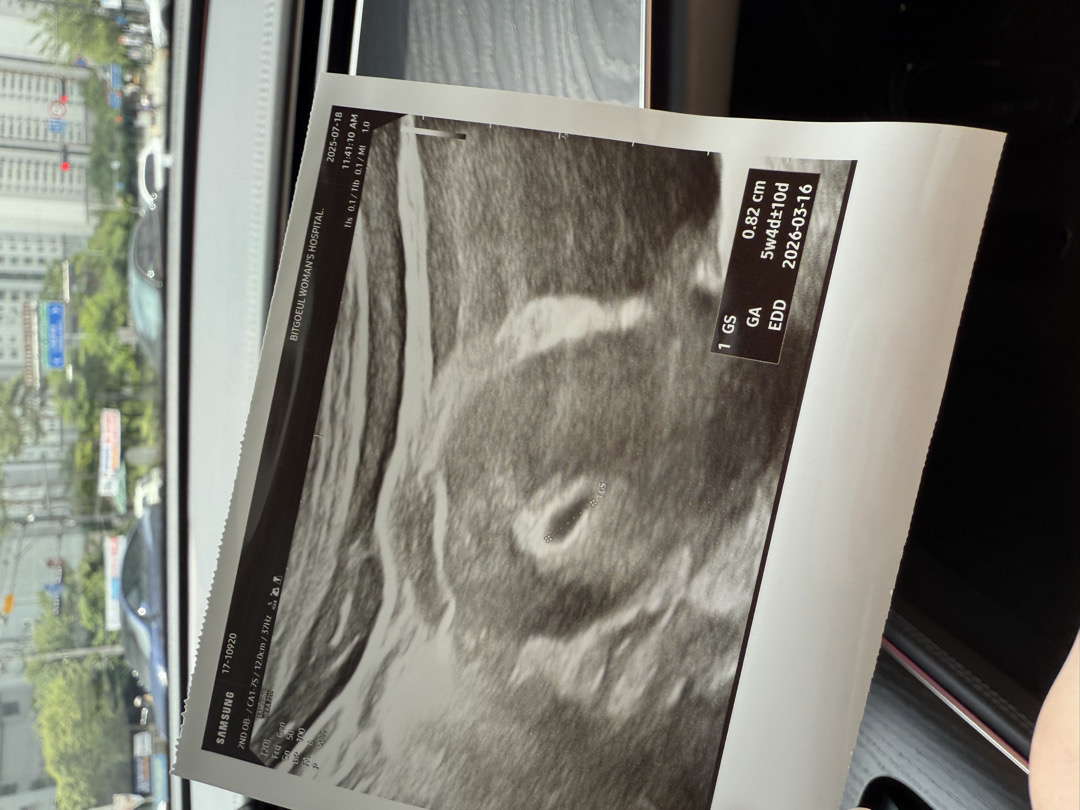

5주 4일차 애기집 집들이 하고왔어요~~~! 애기집 자리 넘 잘 잡혔다구 하네용 담주 심소 들으러가요 ㅎㅎㅎㅎㅎ